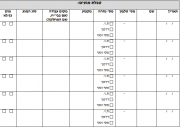

רשימת קבצים

מתוך ויקירפואה

דף מיוחד זה מציג את כל הקבצים שהועלו.

| תאריך | שם | תמונה ממוזערת | גודל | משתמש | תיאור | גרסאות |

|---|---|---|---|---|---|---|

| 05:46, 19 באוגוסט 2014 | מדידת גובה.png (קובץ) |  |

111 קילו־בייטים | Motyk | 1 | |

| 05:44, 19 באוגוסט 2014 | מדידת אורך בתינוק.png (קובץ) |  |

148 קילו־בייטים | Motyk | 1 | |

| 19:09, 18 באוגוסט 2014 | Bmi1.png (קובץ) |  |

6 קילו־בייטים | Motyk | 1 | |

| 17:29, 11 באוגוסט 2014 | BCC-01.png (קובץ) |  |

209 קילו־בייטים | Motyk | 1 | |

| 17:27, 11 באוגוסט 2014 | BCC-SMO.png (קובץ) |  |

326 קילו־בייטים | Motyk | 1 | |

| 16:50, 11 באוגוסט 2014 | Melanoma-06.png (קובץ) |  |

119 קילו־בייטים | Motyk | 1 | |